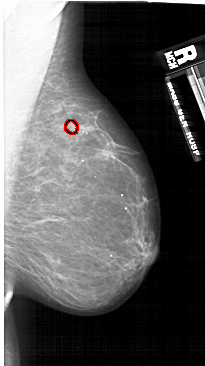

A_1689_1.LEFT_MLO

LEFT_MLO LINES 5941 PIXELS_PER_LINE 3706 BITS_PER_PIXEL 12 RESOLUTION 43.5 NON_OVERLAY

FILE: A_1689_1.RIGHT_MLO.OVERLAY

TOTAL_ABNORMALITIES 1

ABNORMALITY 1

LESION_TYPE MASS SHAPE OVAL MARGINS CIRCUMSCRIBED

ASSESSMENT 4

SUBTLETY 3

PATHOLOGY BENIGN

TOTAL_OUTLINES 1

BOUNDARY